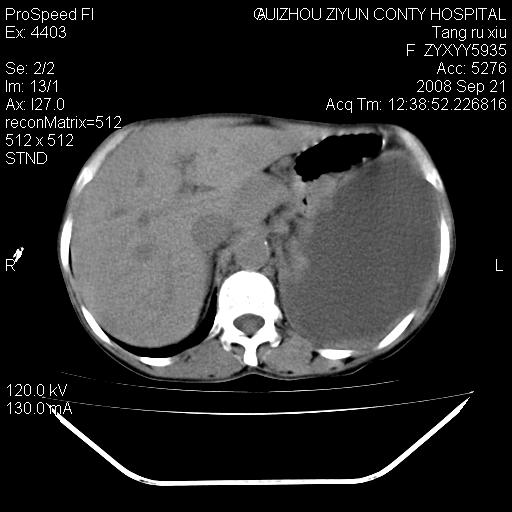

肝脏大小形态尚可,其实质内可见多发大小不等的低密度影,边缘模糊。肝门区结构紊乱,腔静脉腹主动脉旁可见多发软组织密度影,部分融合成团块状,并向下延伸。胰腺及十二指肠结构显示不清。腹腔内脐后肠管走形僵硬,管壁可见增厚。盆腔内可见多个淋巴结影。所扫层面左侧胸腔可见大量弧形水样密度影,其内侧可见被压缩的肺组织影。左侧胸壁可见一小结节样软组织密度影,边缘模糊。心脏纵隔向右侧移位。心脏包膜内可见囊样低密度影,其内侧心房室周围可见一圈气体样密度影。纵隔内大血管旁可见多发软组织团块影,部分融合。

1.腹膜后淋巴瘤侵及肝脏,肺内及纵隔内多发转移。2.左侧大量胸腔积液并压缩性肺不张。3.心包脓肿可能,转移不除外。4.脐后局部肠管管壁增厚,考虑炎症可能,肿瘤不除外。

1)考虑左侧肺癌侵犯纵隔,左侧胸膜、肝脏及腹膜后淋巴结转移。2)左侧胸腔积液。3)心包积液。

支持左侧肺癌伴多发转移。左胸腔积液及左肺不张。